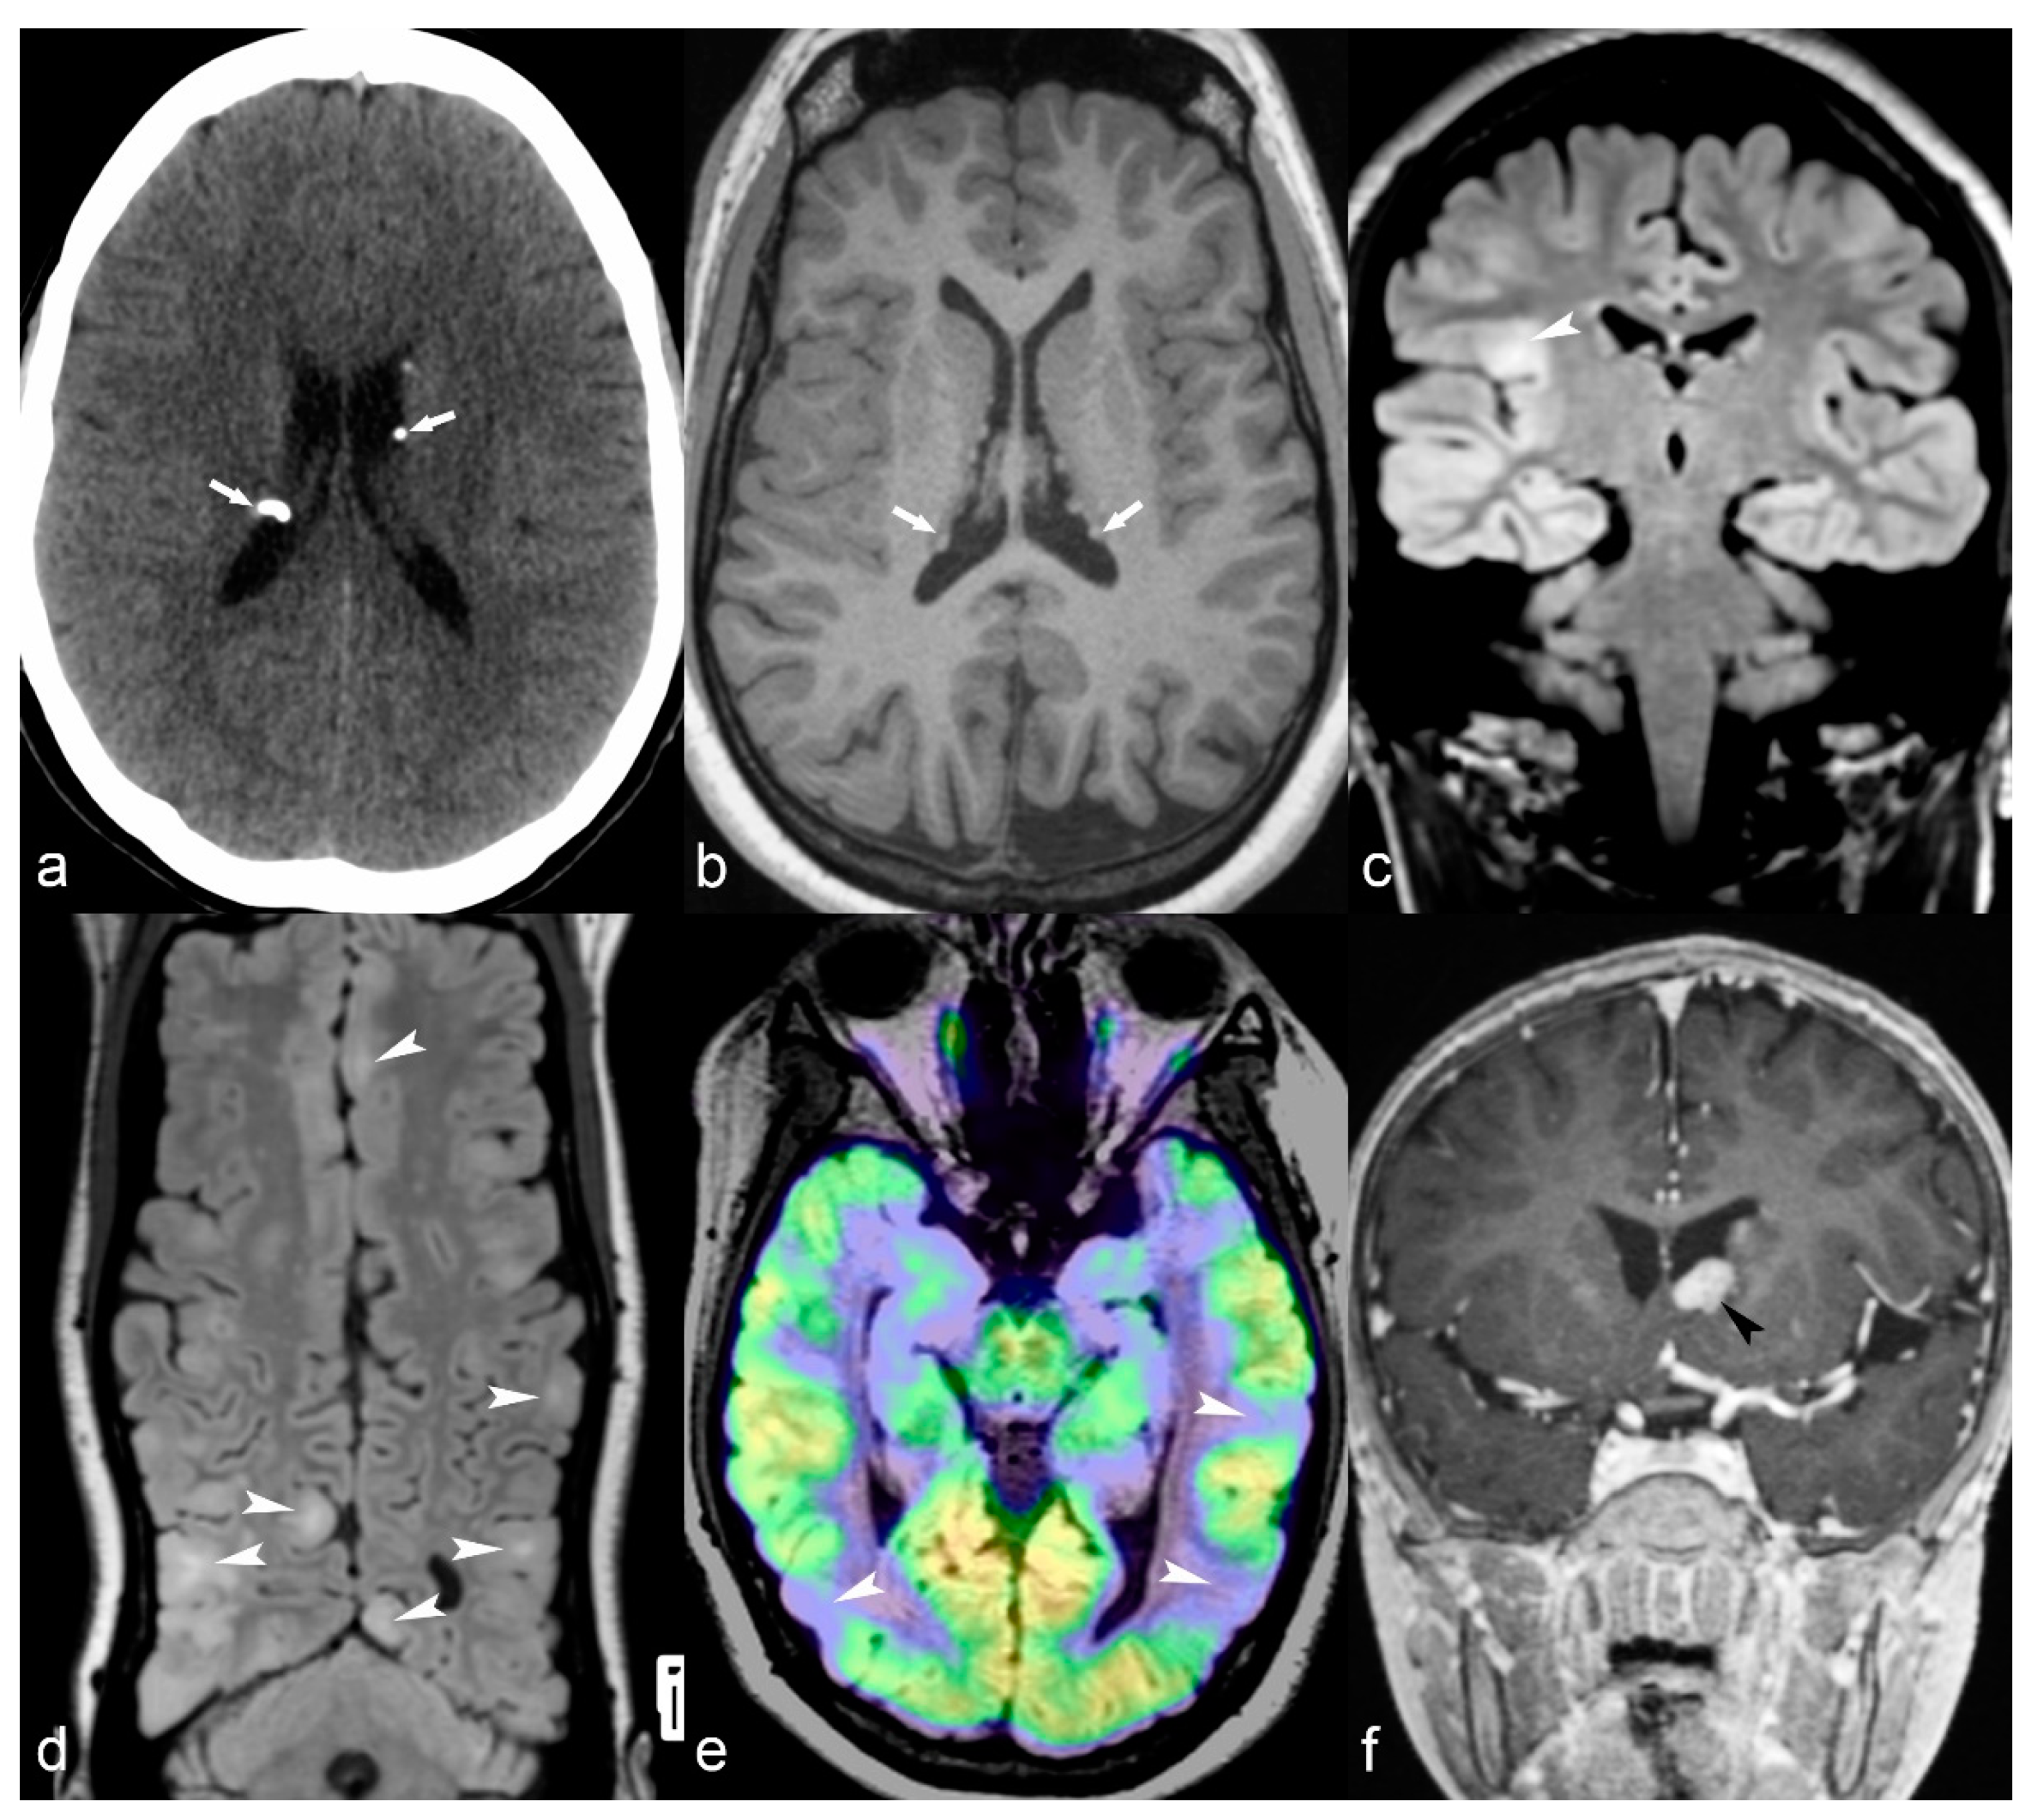

Figure 7.

(a) 25-year-old female with Tuberosis Sclerosis Complex (TSC). Axial CT image (a) shows multiple calcified subependymal nodules (arrows). (b–e) Another 23-year-old female with TSC. Axial T1 weighted image (b) showing multiple subependymal hyperintense nodules (arrows). Coronal FLAIR (c) with curvilinear multiplanar reformat (d) shows multiple cortical tubers with radiating subcortical white matter hyperintensity (arrowheads). PET CT (e) shows hypometabolic areas corresponding to cortical tubers in bilateral occipito-temporal and left temporal region (arrows). (f) 14-year-old male with TSC. Coronal reformat of 3D T1 post contrast image (black arrowhead) shows enhancing subependymal giant cell astrocytoma abutting the floor of frontal horn of left lateral ventricle.